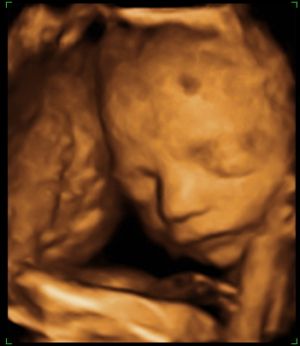

Holnap írok, addig néhány kép:

Kép 3-asban

Kép A gondolkodó